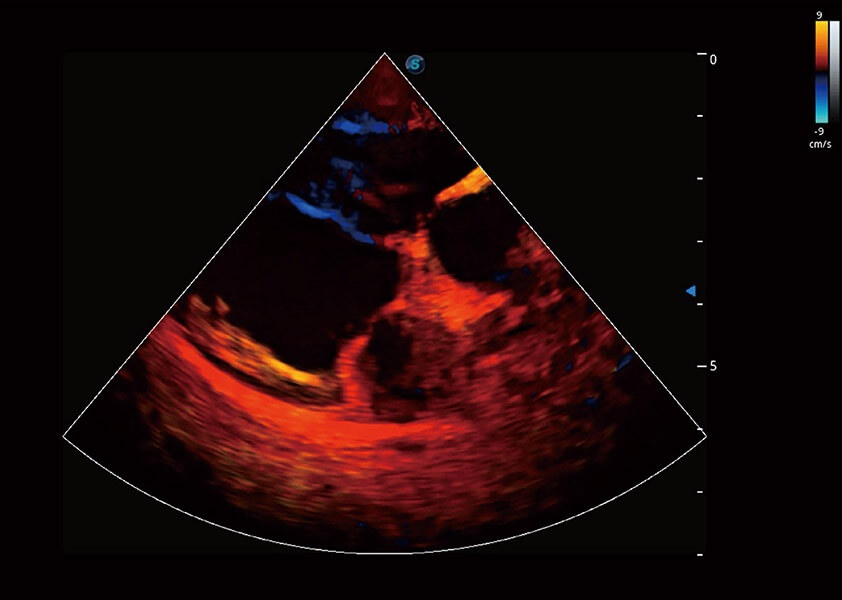

ProPet 60 作为一款高端台式动物超声设备,为动物医生的日常诊断提供了一系列贴合动物临床需求、解决临床实际问题的高级成像功能。凭借全系列高清探头,满足医生对腹部、心脏、生殖、浅表、肌骨等成像的所有需求,切实帮助您提升检查效率,提高诊断信心。

兽用彩色多普勒超声诊断系统

动物是人类最亲密的朋友和最值得信赖的伙伴。九州酷游也一直致力于探索动物专用的超声影像解决方案。 全新推出的ProPet系列,是九州酷游在动物超声影像智能化、专业化、精准化的一次跨越式革新。动物不能用言语来表述自己的不适,通过超声影像,ProPet系列搭建了动物医生与不同物种沟通的“桥梁”,为动物医生注入了“治愈之力”。